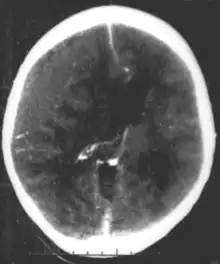

Epidural hematoma as seen on a CT scan with overlying skull fracture. Note the biconvex shaped collection of blood. There is also bruising with bleeding on the opposite side of the brain.

Epidural hematomas usually appear convex in shape because their expansion stops at the skull's sutures, where the dura mater is tightly attached to the skull. Thus, they expand inward toward the brain rather than along the inside of the skull, as occurs in subdural hematomas. Most people also have a skull fracture.[3]